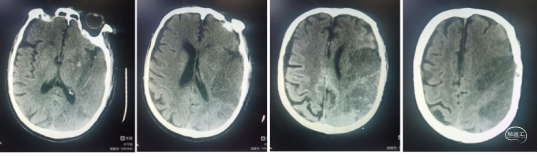

典型病例1: 患者,mshq 男性,44岁,“突发右侧上下肢无力,言语含糊”,溶栓后肢体肌力4-级,搀扶行走。经基层医院静脉溶栓后转入我院。外院核磁显示:左侧侧脑室后角梗塞。MRA显示:C4-C5段以远血管显影浅淡。

转入我科后,患者肢体较溶栓后略有加重,右下肢肌力3级,上肢2级。造影显示:左侧颈内动脉C1段呈火苗样窜动,提示:远端闭塞可能。说明病情在持续加重,可能为血栓堆积闭塞了血管。

术后24小时患者言语清晰,右侧上下肢肌力3+级。复查CT无明显血栓逃逸梗塞和出血征象。